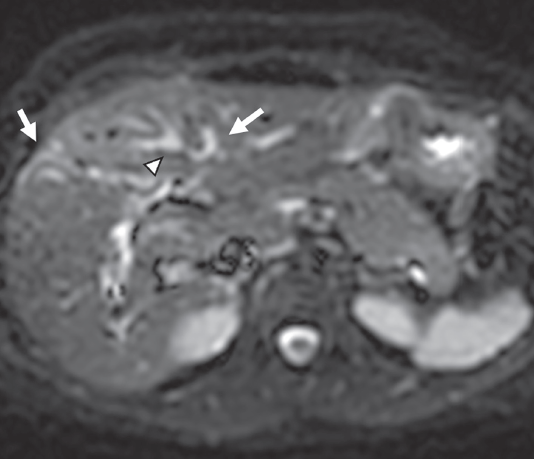

Ante la posibilidad moderada de coledocolitiasis y pancreatitis aguda, se solicitó colangiorresonancia en donde se observaron imágenes compatibles con derivación bilioyeyunal antecólica con anastomosis del hepático derecho anterior, posterior e izquierdo independientes (figuras 1 y 2), y datos de colangitis. Se observó dilatación de la vía biliar distal en el segmento IV con retracción de la cápsula focal (figura 3).

Imágenes: A. Lomas Guim et al.